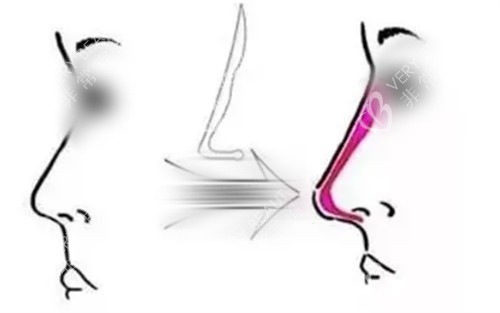

这种缓慢吸收且具备可溶解性的特点,让画缇轮廓针在面部轮廓塑形上有着独特优势。

一方面,它能提供相对持久的塑形作用,帮助求美者塑造理想的面部轮廓;另一方面,如果患者对注射后的结果不满意,或者出现了任何异常反应,医生可以通过相应的手段将其溶解掉,降低了美容风险。